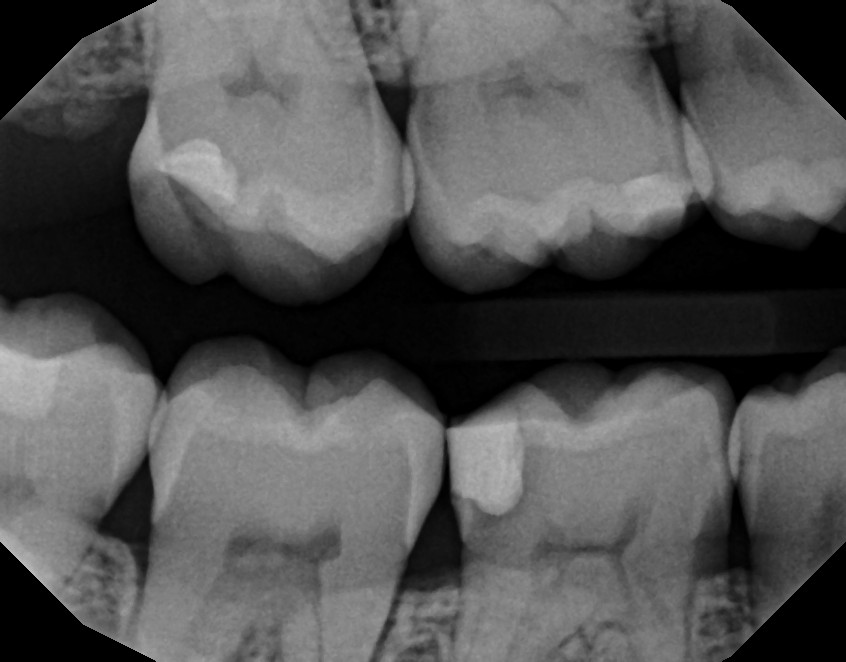

ich habe letzte Woche eine neue Füllung bekommen, weil sich unter der alten Karies befand. Inzwischen war ich bei einem anderen Zahnarzt, der meinte, auf dem Röntgenbild sei weiterhin Karies unter der neuen Füllung zu sehen.

Können solche Ränder oder Schatten auf dem Röntgenbild auch andere Ursachen haben, oder deutet das tatsächlich auf verbliebene Karies hin?

das ist keine neue karies, denn so schnell geht das nicht, da ist karies nicht ganz entfernt worden und somit ist die füllung undicht. am besten mit dem behandler reden, vielleicht machte das vorgehen sinn, vielleicht hat er es einfach nur übersehen, dann eben neu machen.